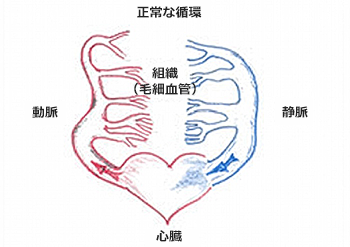

先天的な病気と言われており、母体にいるときから、既に形成されていると考えられています。本来、人間の血管の構造には、大きく分けて「動脈」と「静脈」があります。心臓から酸素をたっぷり含んだ血液は、「動脈」を通って、脳、腎臓、肝臓などの臓器に送られ、臓器の中の「毛細血管」という構造に入ります。ここで組織に酸素を送り、不要な二酸化炭素を吸収しながら、「静脈」へと流れ、心臓に血液が戻っていきます。また、この「毛細血管」を血液が通ることにより、「動脈」を通ってきた血液の圧が下がり、「静脈」を流れる血液の圧が低くなります。AVMにおいては、脳の血管構造の一部で、「毛細血管」を介さずに「ナイダス」と呼ばれる異常な血管網を介して、「動脈」と「静脈」が交通しています。このために、本来は低圧系である「静脈」の中を圧が下がっていない「動脈血」が流れる状態になっています。このために、高圧に慣れていない「静脈」が拡張して太くなったり、静脈瘤を形成して破裂をしたりすることで、脳出血やくも膜下出血を来すことがあります。また、AVMの部分は、血流が非常に多く早くなるため、周囲の正常脳への血流を奪い取ってしまうことがあり、これによる正常脳の慢性的な血流低下をきたし、二次的に脳組織の変性を来たし、痙攣発作を起こすこともあります。